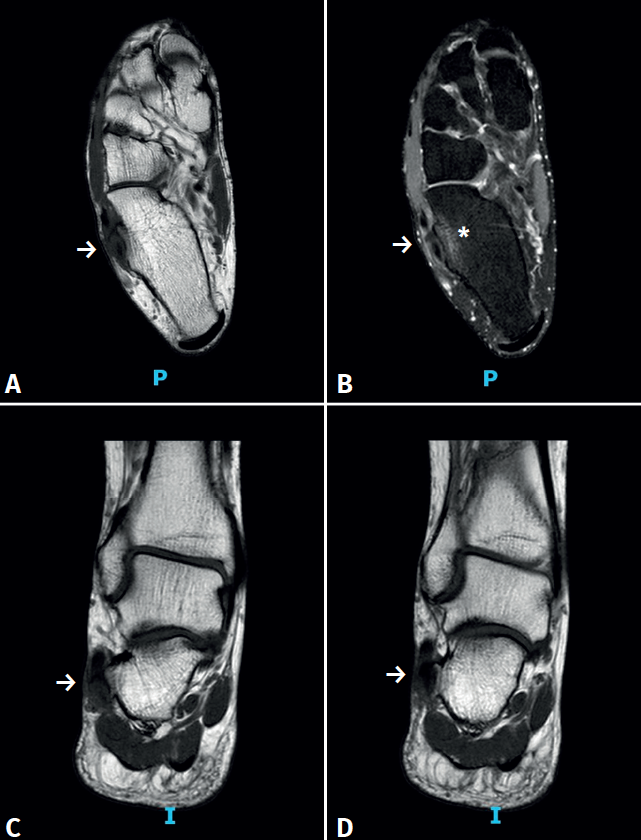

rpt.3702.fs2302004-figura2.png

Figura 2. Resonancia magnética del pie derecho sin contraste. A y B: cortes axiales en secuencias T1 y STIR que evidencian la presencia de tenosinovitis del tendón peroneus longus (flecha), el cual se encuentra en íntimo contacto con un tubérculo peroneal que presenta edema óseo (asterisco) y que tiene forma doble convexa según lo descrito por Vosoughi et al.; C y D: cortes sagitales en secuencia T1 que evidencian el tubérculo lateral hipertrófico con tenosinovitis del tendón peroneus longus (flecha).

Se solicitan radiografías con carga que evidencian la presencia de un pie cavo varo (Figura 1) y una resonancia magnética sin contraste que muestra una rotura parcial antigua del ligamento talofibular anterior, una exostosis ósea en el borde lateral del calcáneo de 6,2 mm, con edema óseo adyacente y un engrosamiento significativo de un segmento de 3 cm del tendón peroneus longus en relación con la exostosis previamente descrita (Figuras 2 y 3).

En nuestro caso, la morfología presente fue un tipo doble convexo que, como se mencionó anteriormente, estaría presente en solo el 24% de la población y la altura fue de 6,2 mm, lo que confirma la presencia de una hipertrofia de esta estructura. La medición de la altura fue realizada en el corte axial de resonancia en la secuencia T1, desde el vértice del tubérculo hasta una línea trazada en la cortical lateral del calcáneo, según lo descrito por Saupe et al.(13).